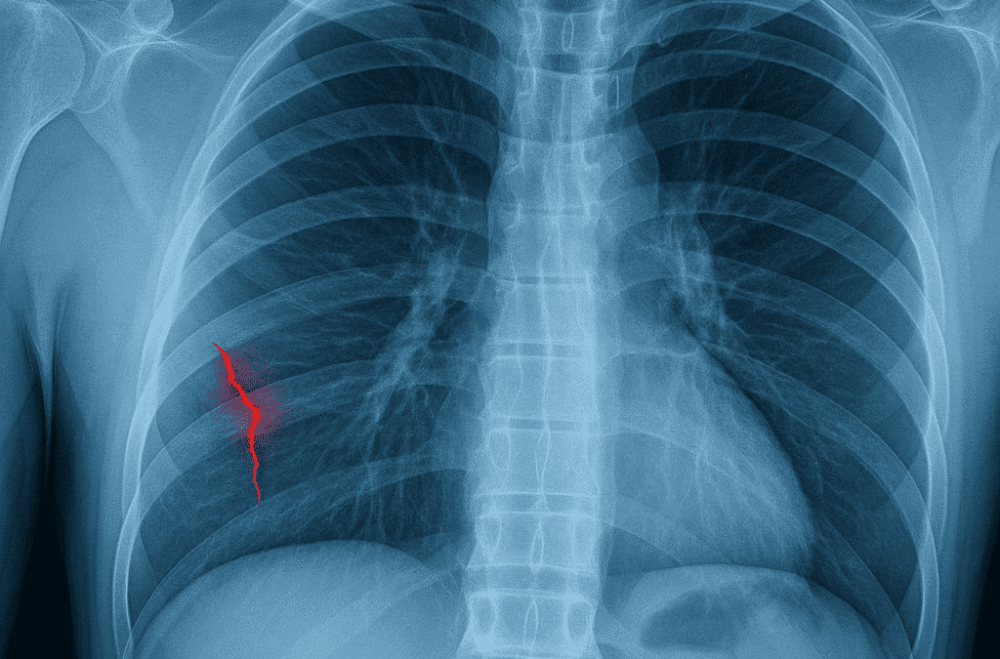

Рентген або КТ – єдиний надійний спосіб точно відрізнити забій, тріщину й перелом. Усе інше – припущення.